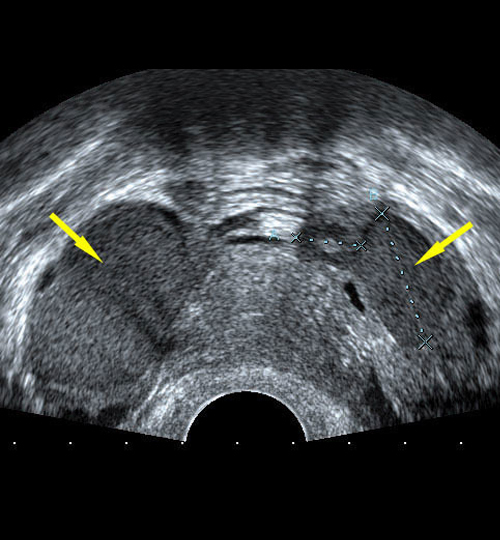

Affectant 10 à 15 % des femmes en âge de procréer, avec une incidence atteignant 50 % chez les femmes infertiles, cette pathologie est définie par la présence de glandes ou de stroma endométrial en dehors de l’utérus. Les premiers symptômes apparaissent à l’adolescence et ont des répercussions importantes sur la qualité de vie, c’est pourquoi toute dysménorrhée sévère doit être explorée chez l’adolescente.

Mais L. L’endométriose digestive.  Rev Prat 2022 ;72(2) ;193 - 7.